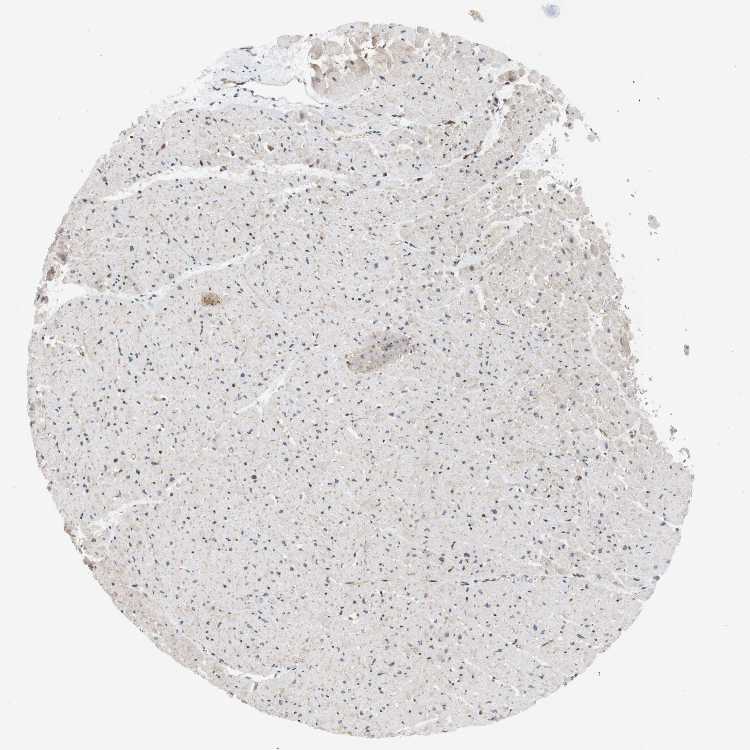

HEART MUSCLE - Antibody stainingi

Antibody staining in the annotated cell types in the current human tissue is reported as not detected, low, medium, or high, based on conventional immunohistochemistry profiling in selected tissues. This score is based on the combination of the staining intensity and fraction of stained cells.

Each image is clickable and will lead to virtual microscopy that enables deeper exploration of all samples and also displays staining intensity scores, fraction scores and subcellular localization as well as patient and tissue information for each sample.

Antibody HPA042097Antibody CAB005044Antibody CAB009803

Cardiomyocytes Not detectedNot detectedLow